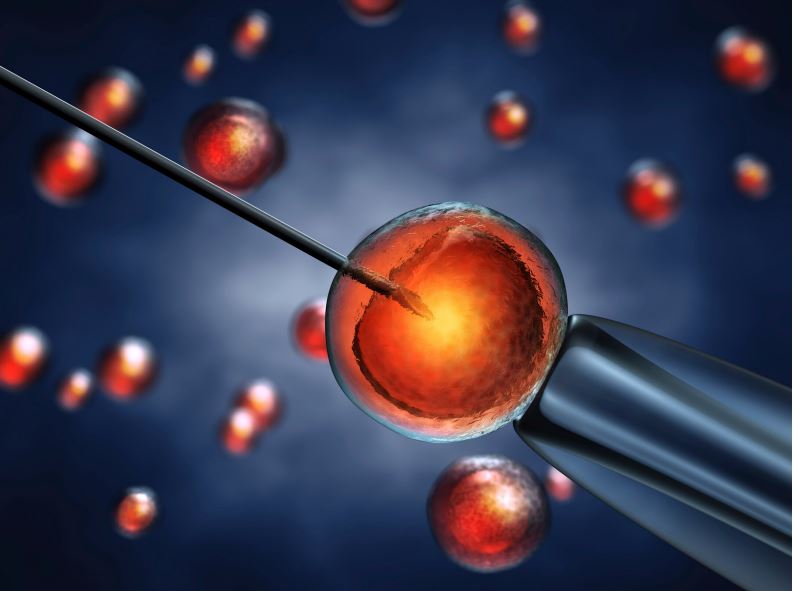

Procréation Médicalement Assistée